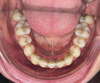

PENDANT